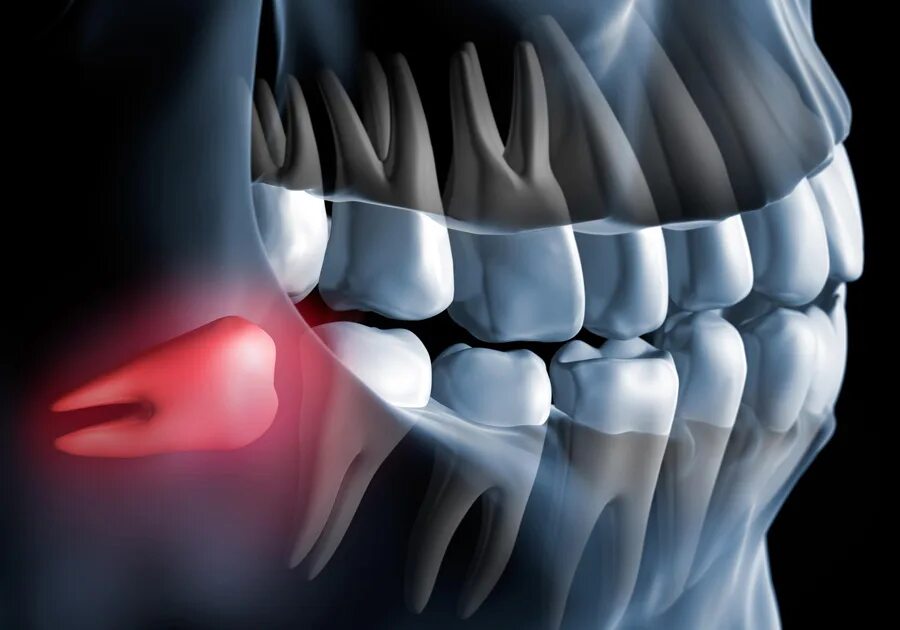

Зуб дистопирован